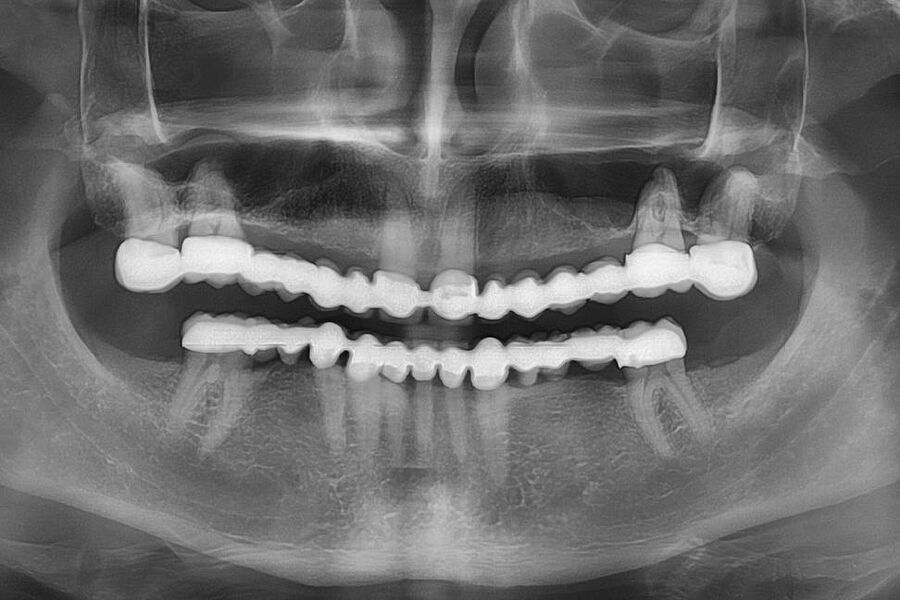

Eine neue Kasuistik zur Rehabilitation bei einer sehr komplexen Ausgangslage in der ästhetischen Zone ist in der Zeitschrift Implantologie des Quintessenz-Verlages erschienen. Als einzige deutschsprachige Zeitschrift aus dem zahnmedizinischen Bereich verfügt die Implantologie über einen kleinen Impact Factor. Konkret stellen die beteiligten Autoren in ihrem 13 Seiten umfassenden Case Report ein synoptisches Behandlungskonzept zur Rekonstruktion zu Verlust gegangener Hart- und Weichgewebe vor. Sie zeigen bei einer 31-jährigen Patientin die Umsetzung einer restaurativen Rehabilitation im anterioren Oberkiefer nach Zahnverlust und beidseitigen Nichtanlagen der seitlichen Schneidezähne.

Zeitschrift: Implantologie

Ausgabe: 02/2022, Seiten 203 – 215

Autoren: Dr. Eleftherios Grizas, Dr. Anna Gutbrodt, Dr. Julian Arnold, alle Dorow Clinic Lörrach, Dr. Dr. Hans Ulrich Brauer, M.A., M.Sc., Akademie für Zahnärztliche Fortbildung Karlsruhe